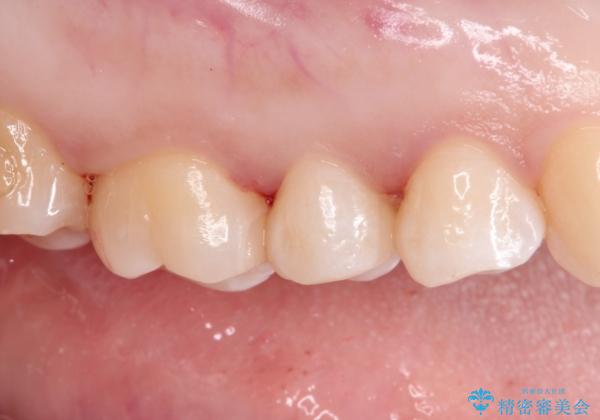

- 金属の詰め物を外して、セラミックインレーを入れたいと来院された患者様です。

奥歯に虫歯も認め、3歯の治療を来院回数2回で終了で終了しています。

当院でのセラミックインレーはすべてe-maxと呼ばれる高強度セラミックにて製作されます。

また、製作方法もプレスと呼ばれる方法を用いることで精度を高めています。